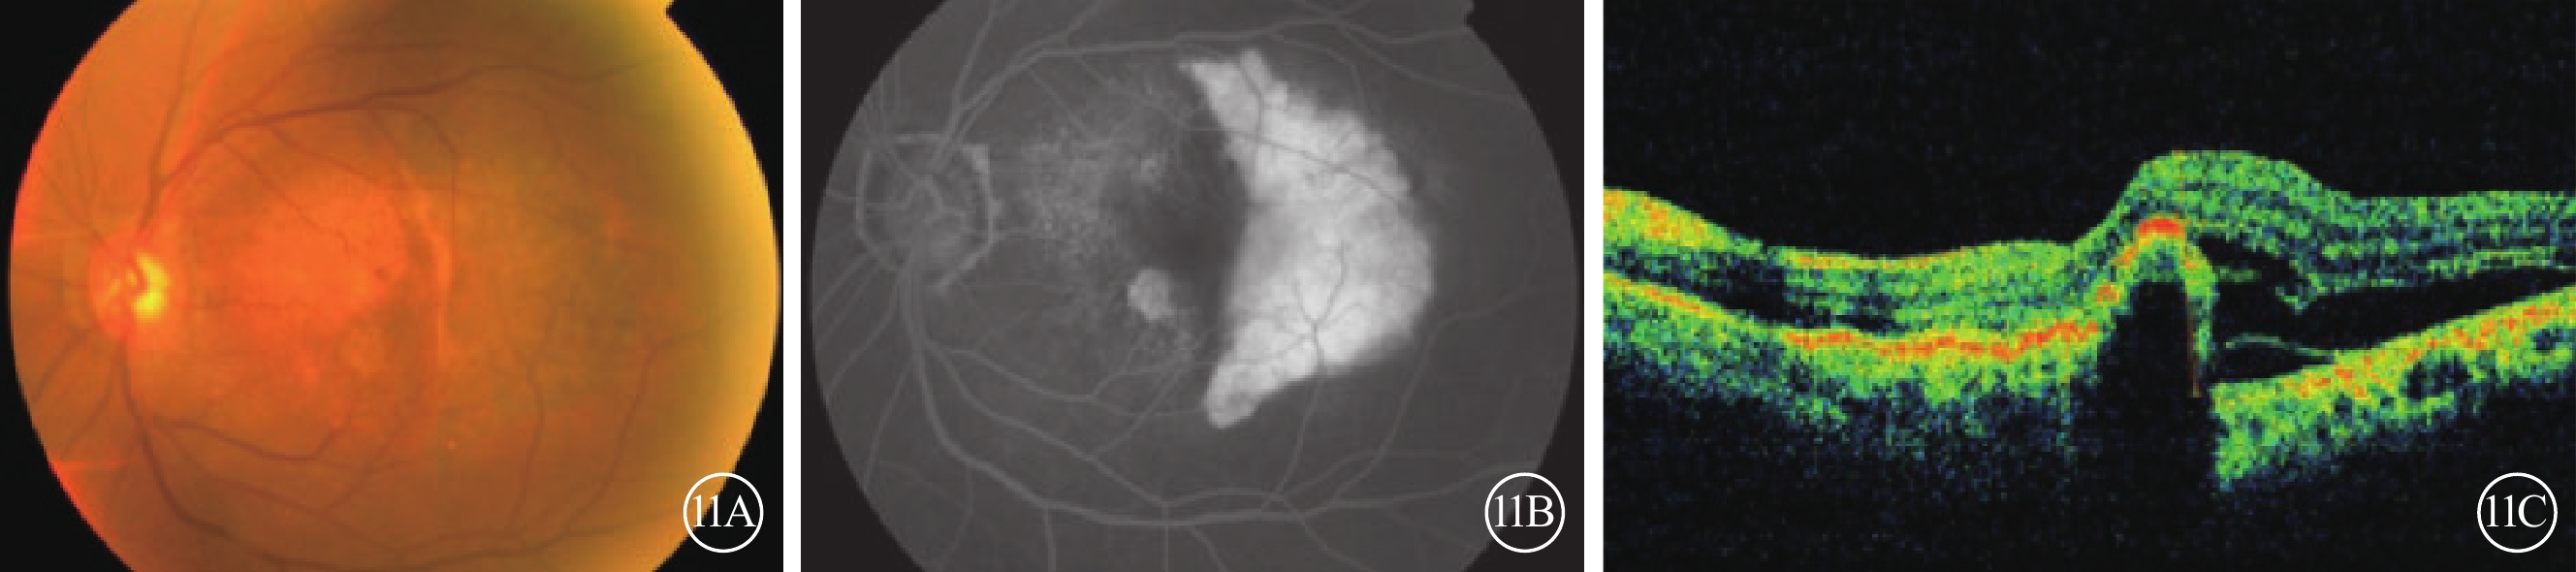

RPE撕裂由RPE層的牽引性開裂引起,牽引力來自于RPE下的纖維血管組織,當牽引力大于RPE單層結構的力度時便導致RPE撕裂[36-37]。撕裂后的RPE邊緣回縮,導致游離端的RPE形成不同程度的堆積,此區域在FFA上呈遮蔽熒光,缺失RPE區域在FFA上呈透見熒光;OCT中顯示為脈絡膜的強穿透性(圖11)。由于RPE缺失或脈絡膜毛細血管萎縮, OCTA可以觀察到來自深層脈絡膜血管的血流信號。

圖11

RPE撕裂患眼眼部檢查像。11A示彩色眼底像,視網膜下病變區色素紊亂。11B示FFA像,撕裂端RPE的堆積呈遮蔽熒光,而缺失RPE區域呈透見熒光。11C示OCT像,RPE層斷裂,其下脈絡膜呈弱反射。RPE:視網膜色素上皮;FFA:熒光素眼底血管造影;OCT:光相干斷層掃描像